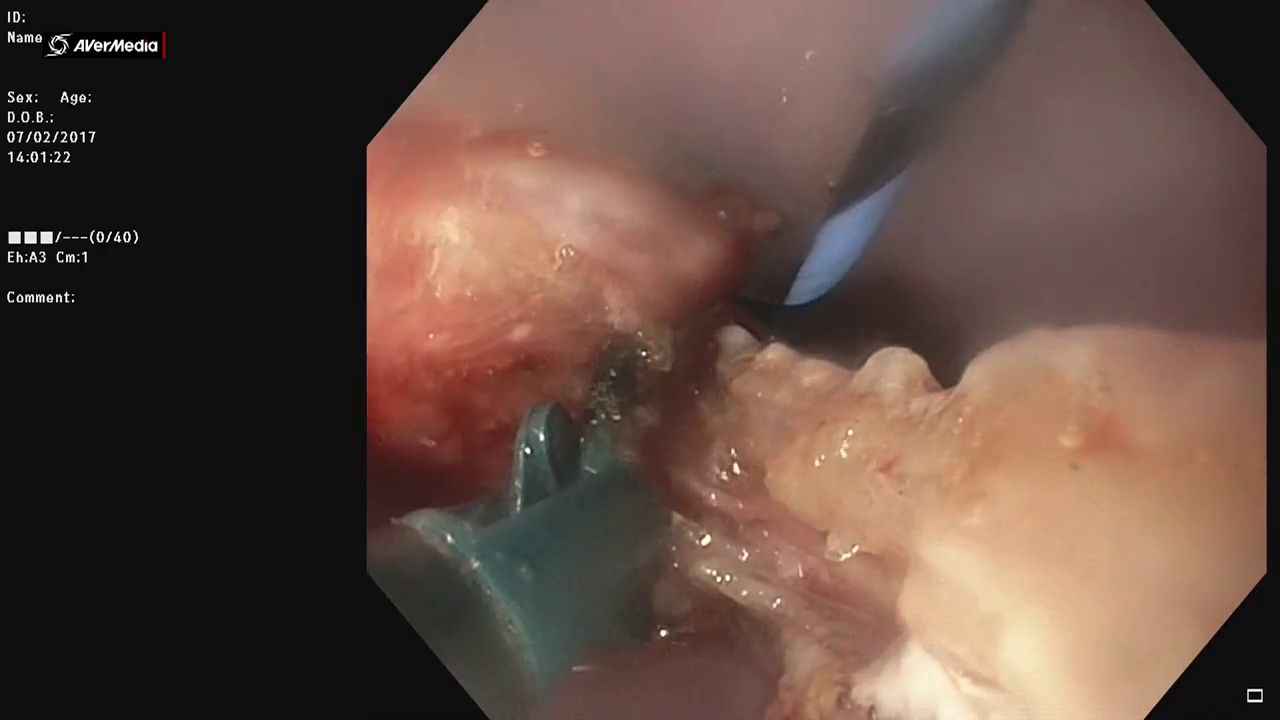

After several weeks we got a diverticuloscopium that we put through a guidewire previously placed in esophagus by gastroscopy. When we insert the diverticuloscopium the septum is seen perfectly.

The diverticulospium is also important because it helps to define the end of the bottom of the diverticulum and where to cut the septum

In this case we use the SB junior’s 3.5 mm dissector with electro surgery parameters defined before. This dissector allows you to rotate and orient the cut with great accuracy.